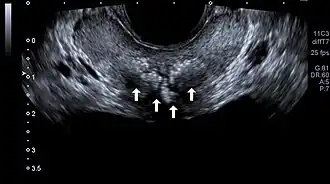

Transrectal ultrasound of prostatic stones in the peri-urethral zone of the prostate

Prostatic calculi (PC), prostatic stones, prostatic calcification or prostatic lithiasis, are hyper-echoic mineral deposits in the prostate that are frequently detected incidentally during transabdominal ultrasonography, transrectal ultrasonography, or computed tomography.[1][2][3]